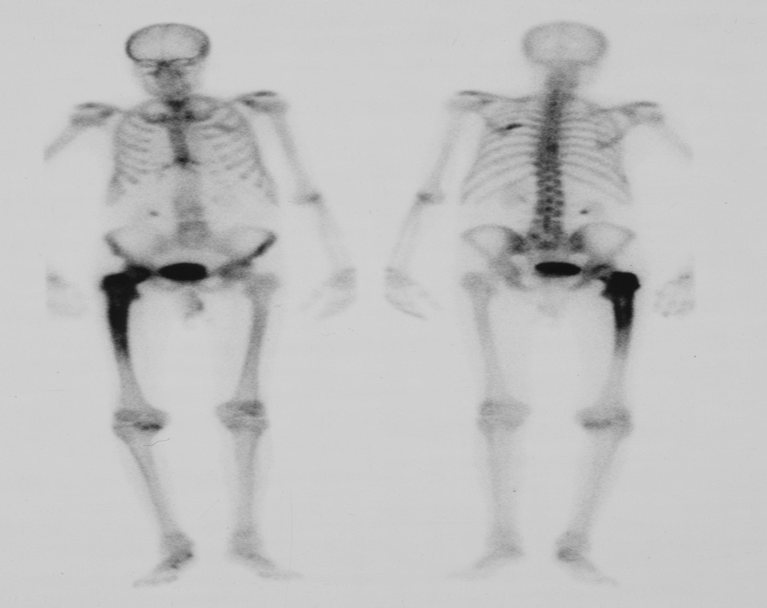

Radionuclide bone scan. The patient has received an intravenous injection of a 99mTc-labelled bone-scanning agent The increased uptake in the femur in this patient was due to Paget’s disease